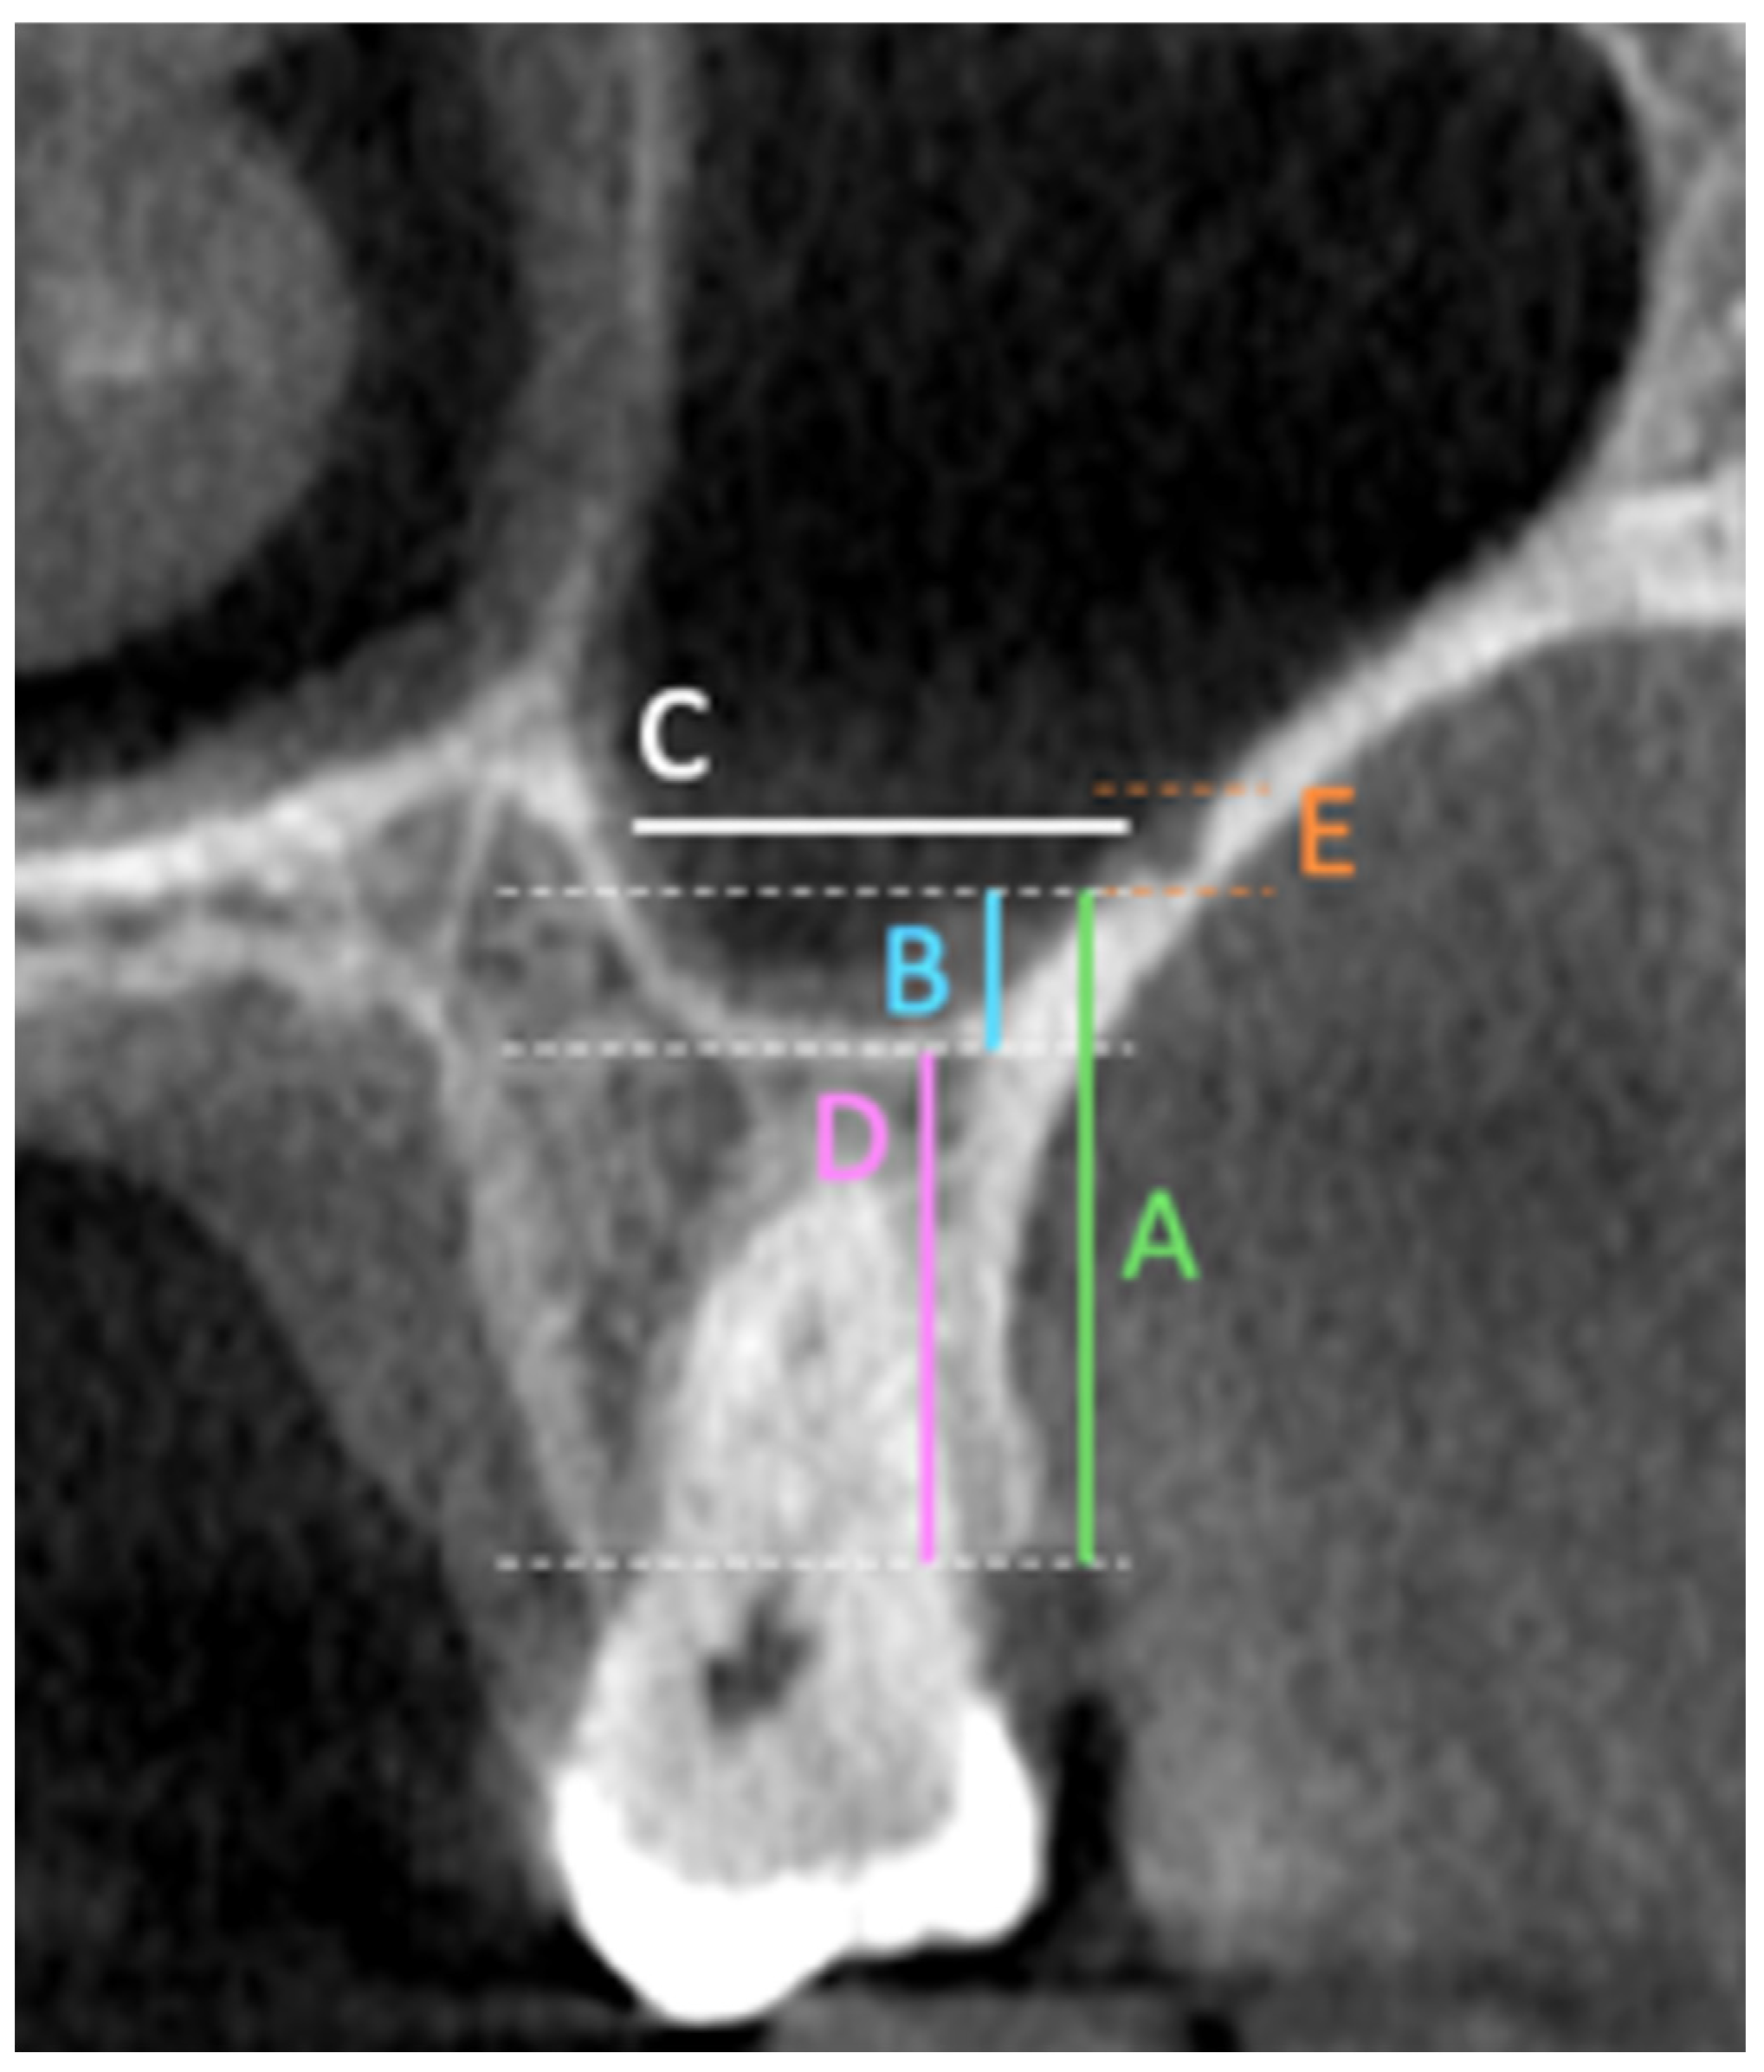

The primary outcomes of this study included multiple linear and categorical measurements obtained from coronal CBCT sections. These outcomes included measuring the fol-lowing in the coronal section: the distance from the artery to the (A) ridge crest, (B) floor of the maxillary sinus, (C) medial wall of the sinus, (D) height of the alveolar ridge, and (E) the diameter of the artery; finally, the presence or absence of the septa in the sinus (

Figure 1). Also, the PSAA’s anatomical location can be categorized as Type A (on the lateral sinus wall’s outer cortex), Type B (intraosseous), or Type C (beneath the Schneiderian membrane) (

Figure 2). All outcomes were recorded separately for premolar and molar regions based on root location or estimated axis in edentulous sites, as shown in

Figure 1 and

Figure 2.

The distance between the PSAA and the alveolar crest was measured at the premolar and molar regions for the right and left sides. The results showed that there was no significant difference between the sides, but significant differences were observed between the premolar and molar regions. The mean distances from the PSAA to the crest in the premolar region were 21.06 ± 6.02 mm on the right side and 20.74 ± 6.55 mm on the left, while for the molar region, the means were 16.17 ± 4.0 and 15.64 ± 4.35 for the right and left sides, respectively, as shown in

Table 4 and

Figure 3.

The position of the PSAA within the maxillary sinus was assessed by measuring the distance to the floor and medial wall of the maxillary sinus. The results showed that the mean distances from the PSAA to the sinus floor in the premolar and molar regions on the right side were 5.91 ± 4.16 mm and 6.18 ± 3.47 mm, respectively, while for the left side they were 5.86 ± 3.97 and 6.31 ± 3.45. The distances from the PSAA to the medial sinus wall were 8.25 ± 3.81 mm (premolar) and 13.02 ± 3.53 mm (molar) on the right side and 8.54 ± 3.76 mm (premolar) and 13.06 ± 3.55 mm (molar) on the left side, as shown in

Figure 4.